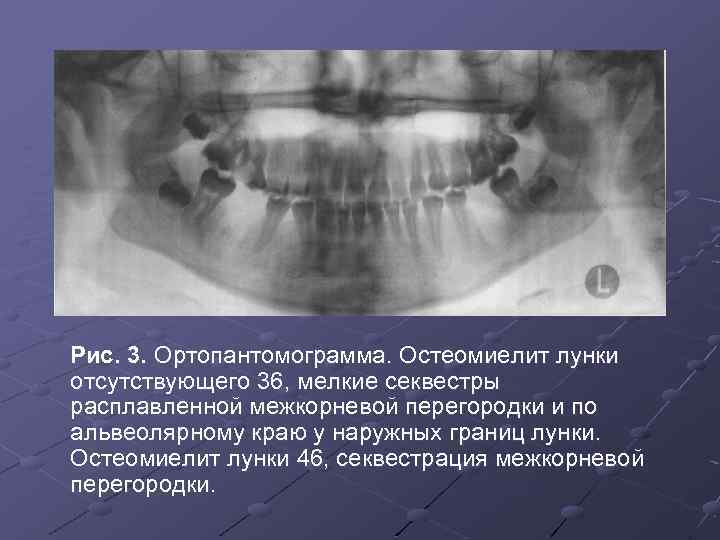

Рентгеновские снимки посттравматического остеомиелита челюсти: Медицинские случаи

Раздел: Образы вокруг